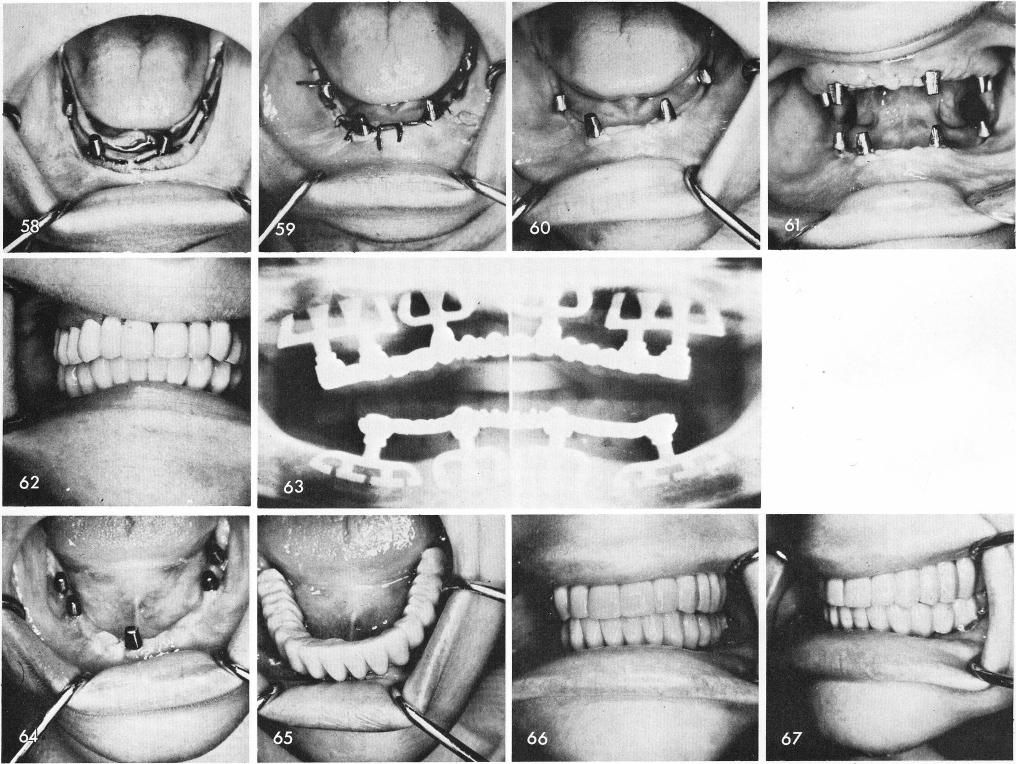

1. The tissues are sutured and immediately after the posts are made parallel to each other, fig.

2. Healing is rapid, figs. 60, 61, and the final prosthesis has been functioning at this date for nearly nine years, fig. 62. The x-ray was an eight year post-operative view, fig. 63.

Many cases have been done with only three blades, the anterior one usually avoiding a deep unhealed socket area or merely an area not having enough bone, fig. 64. The three blades often support the full arch fixed prosthesis as well as four, figs. 65, 66, 67.

1 Post operative x ray of final prosthesis over mandibular implants